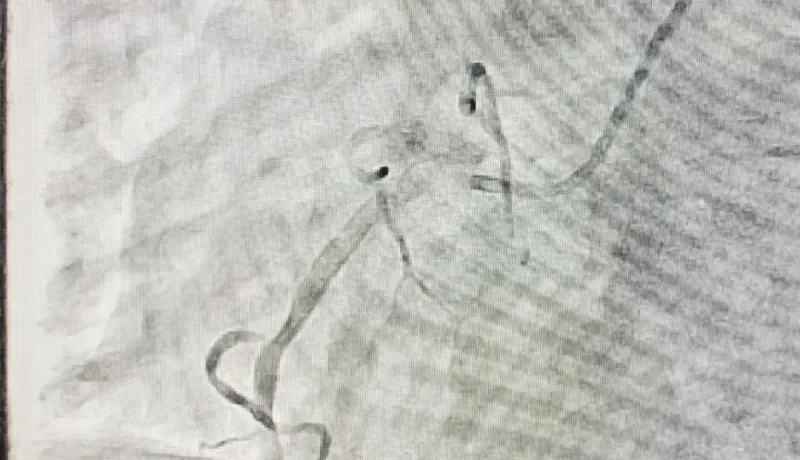

随后的学术交流环节,商洛市中心医院专家团队倾囊相授:孙科主任以《烧伤与创面修复学科建设》为题,系统阐述学科定位、人才梯队建设及多学科协作模式;魏珍护士长围绕《创口治疗中心建设与皮肤护理专业小组发展现状》,解析标准化流程构建与专科护理质控要点;雍波主讲《烧伤急救与治疗》,聚焦黄金时间处置原则、休克期管理与创面早期修复技术;李晓雪针对《重度烧伤患者的精细化护理》,详解液体复苏监测、感染防控及营养支持策略;张芳芳结合《压力性损伤的非手术治疗与互联网+护理服务》,分享新型敷料应用、负压治疗及远程居家护理实践;寇毅通过《压力性损伤的手术治疗》,演示皮瓣移植、清创修复等关键技术适应症与操作规范。